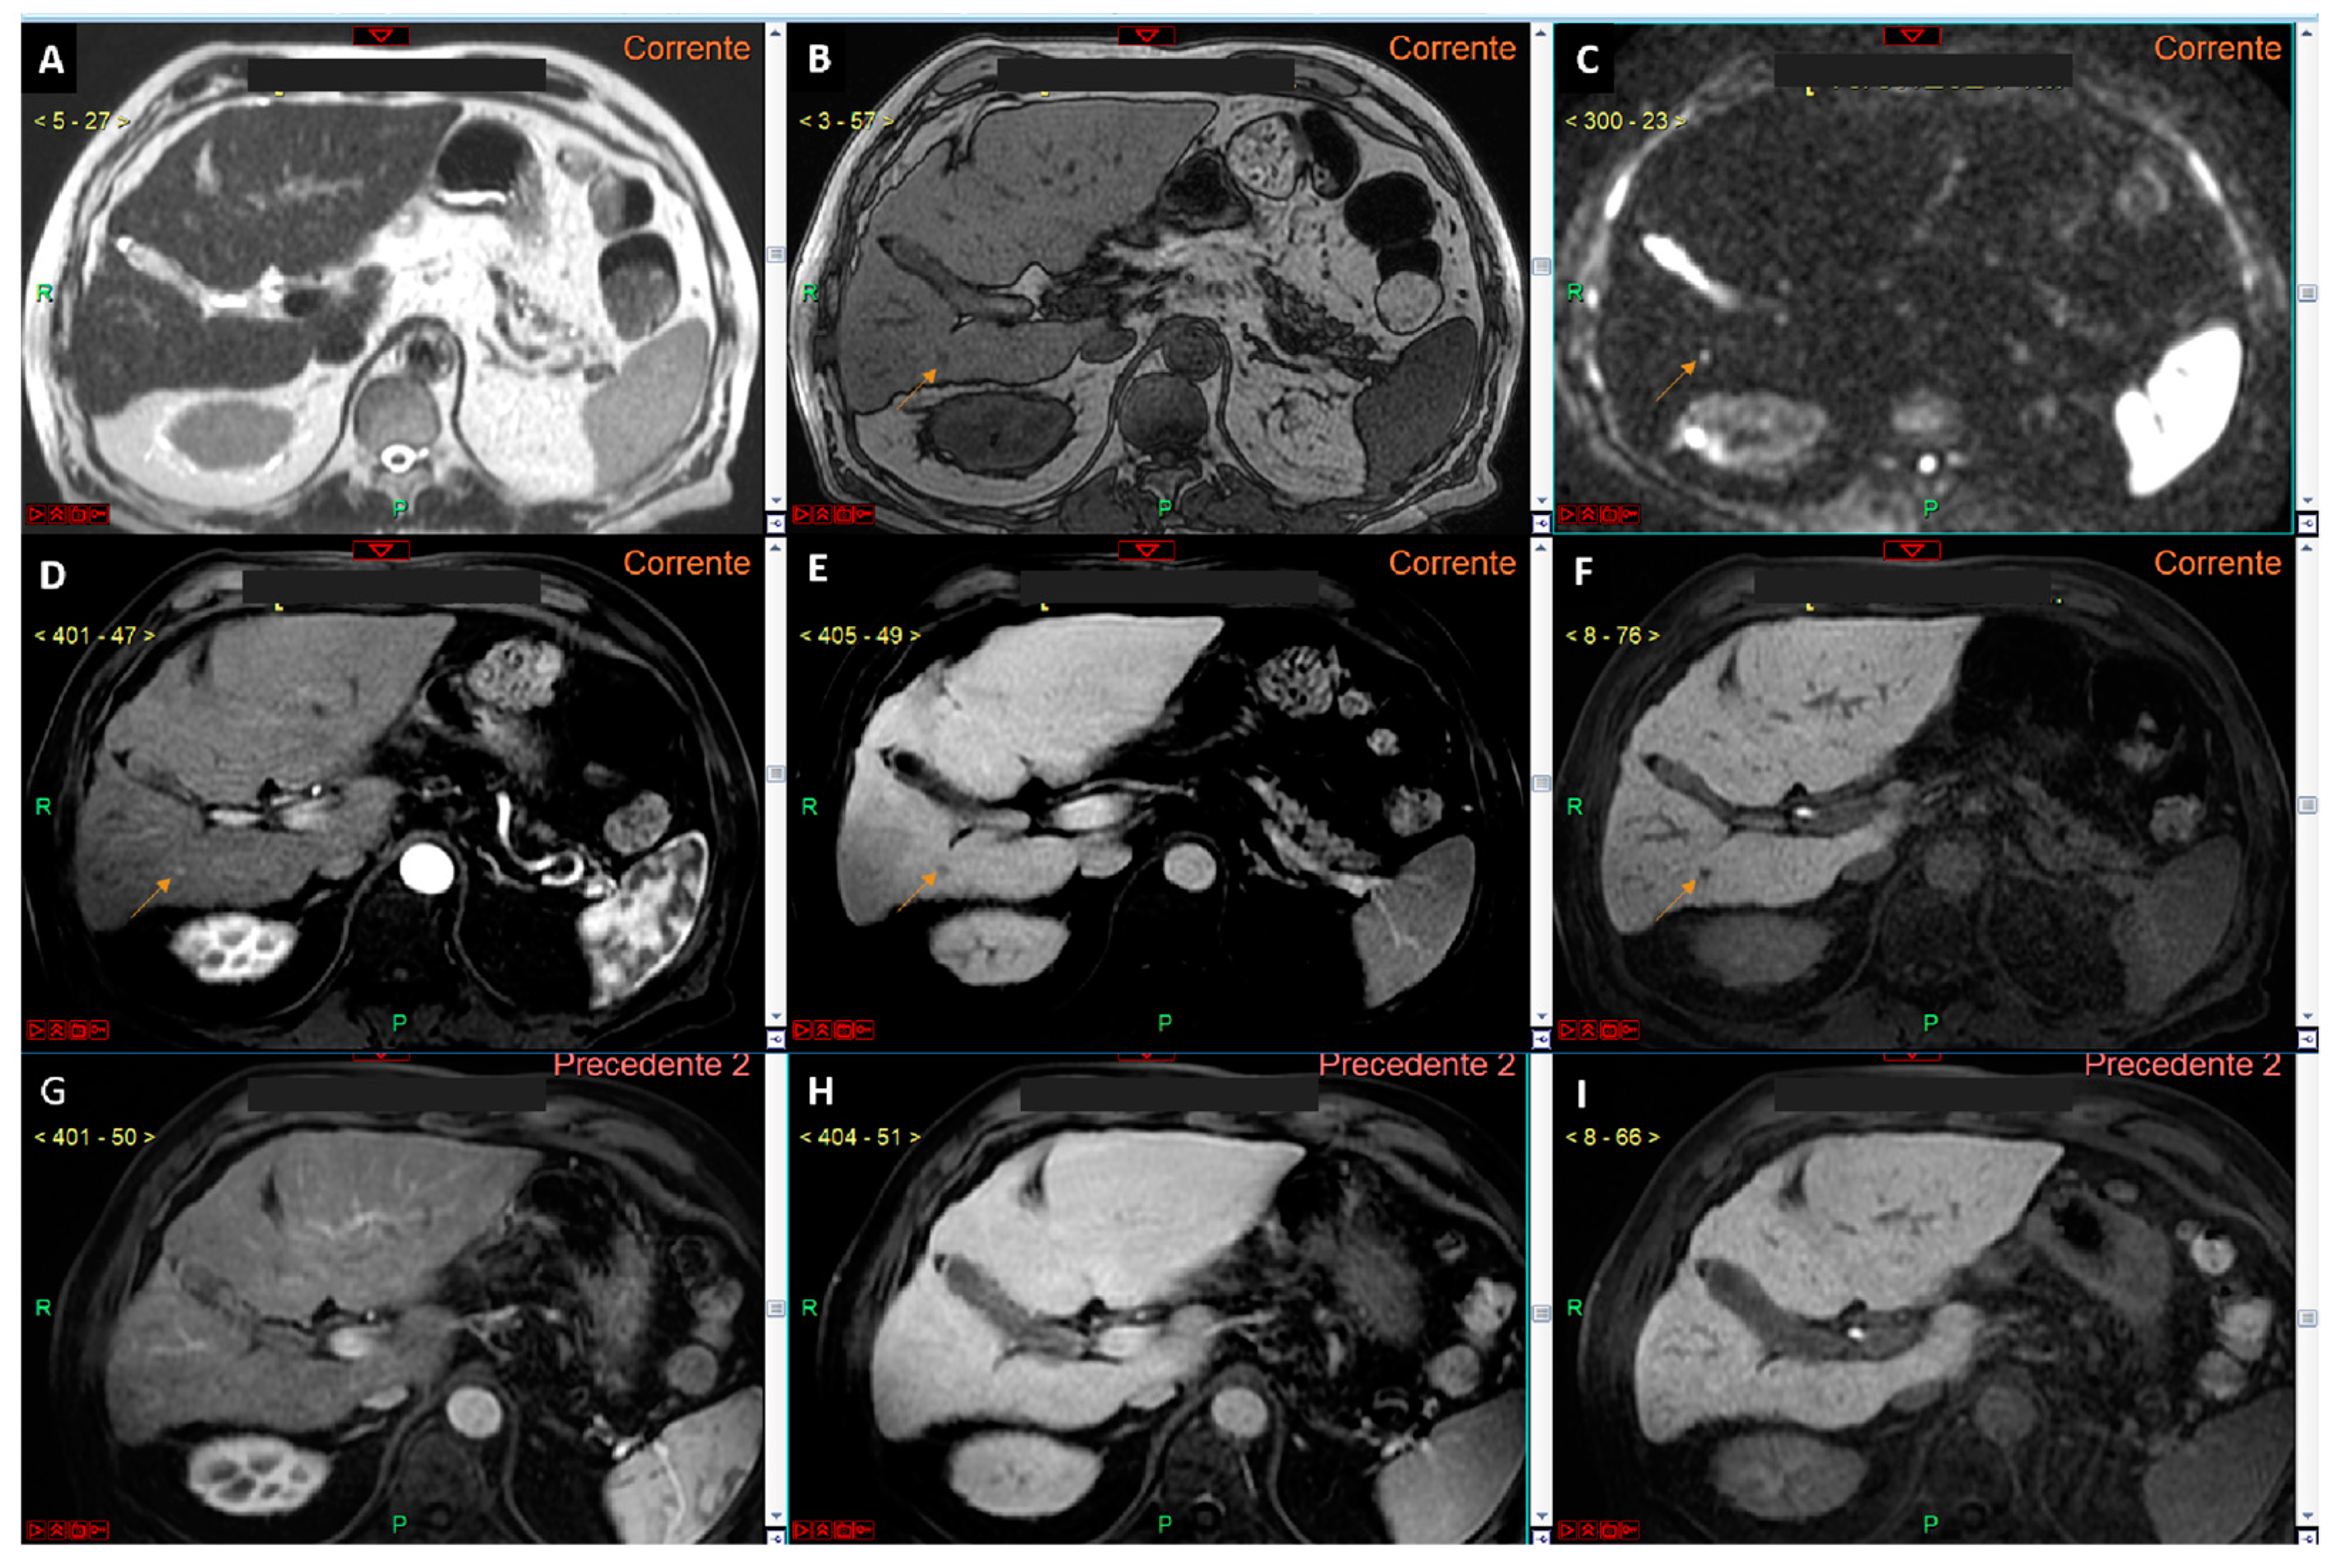

Figure 4.

Panels (A–F) represent a complete liver MRI examination with a hepatospecific contrast agent in a cirrhotic liver. Except for the T2-weighted image (A), the remaining images reveal a lesion of 4.5 mm in the liver segment VI (arrows in (B–F)) with features suspicious for HCC. Specifically, the lesion appears hypointense in the T1 out-of-phase sequence (B), shows signal restriction on diffusion-weighted imaging at a b-value 800 (C), arterial phase hyperenhancement (D), wash-out of contrast media in the venous phase (E), and hypointensity in the hepatobiliary phase (F). Panels (G–I) show a study of the same patient performed one year prior to the current examination, where no lesion in the liver segment VI was observed in the arterial (G), venous (H), or hepatobiliary (I) phases. This study demonstrates that, while the segment VI lesion has imaging features typical of HCC, it cannot be diagnosed as such according to EASL guidelines because its size is <1 cm, despite the previous negative MRI exam. However, if the new diagnostic criteria proposed by Huang et al. (see reference no. [25]) were applied, the lesion could be diagnosed as HCC due to an alpha-fetoprotein level of 37 ng/mL.